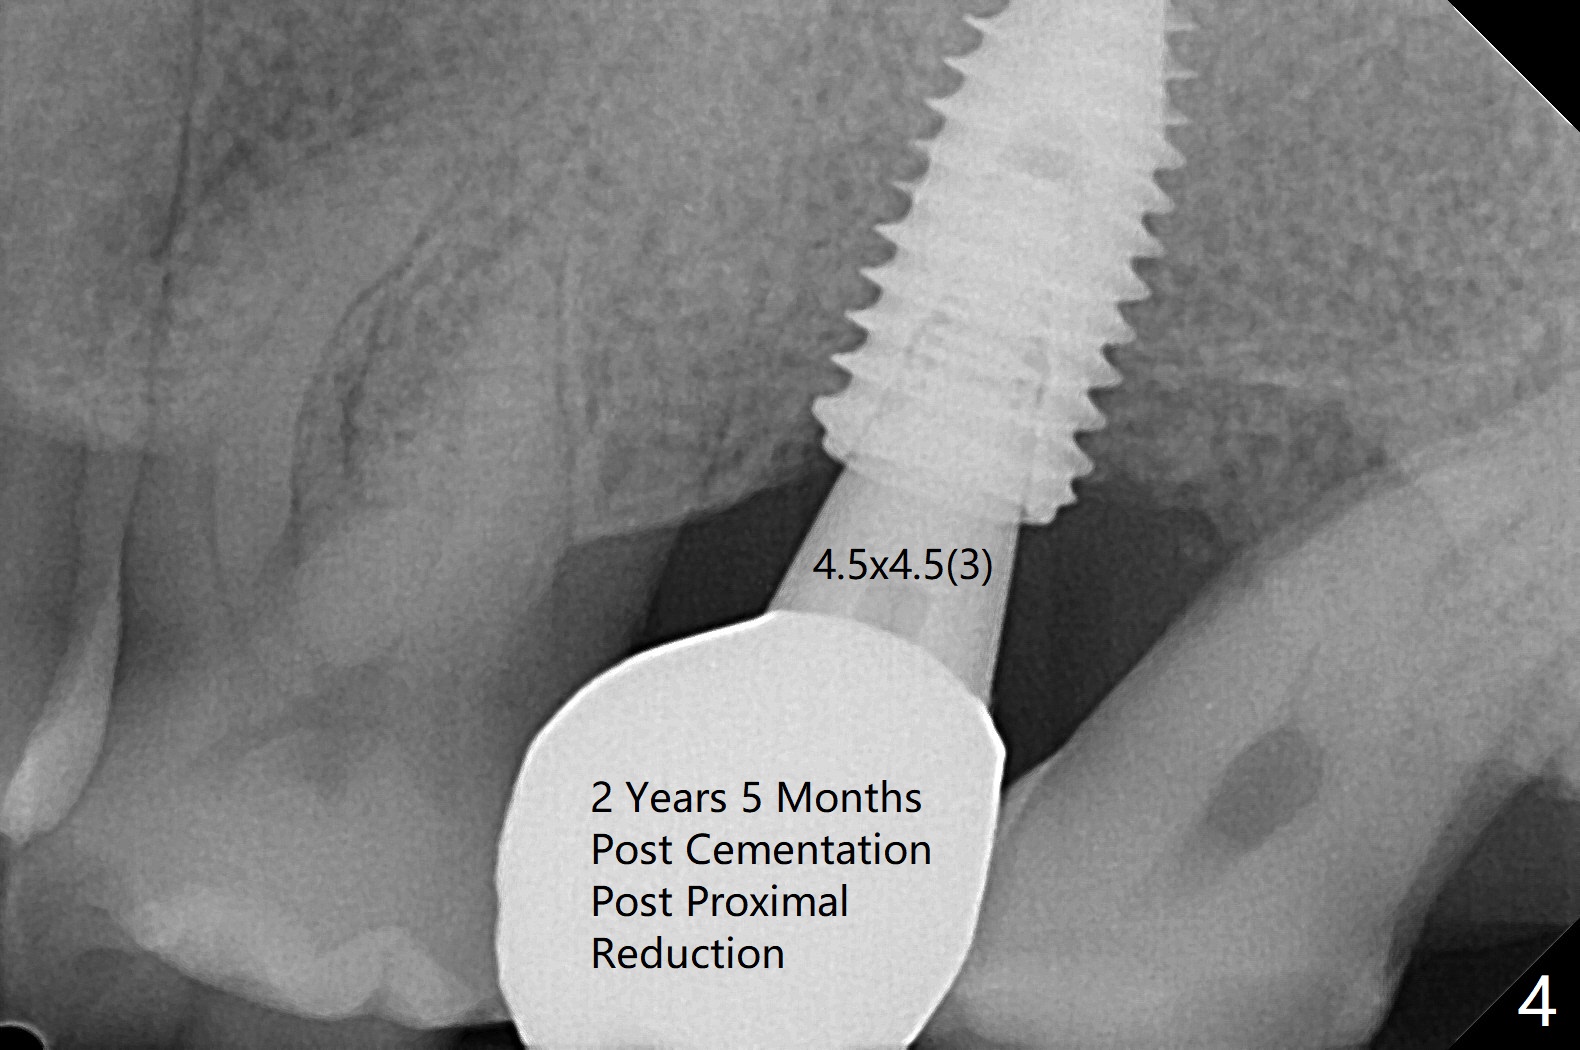

For the narrow mesiodistal space (Fig.3), a 4.5x4.5(3) mm cementation abutment is placed for final restoration. He expresses interest in implants at #29 and 30 or #19. The screw is loose 2 years 5 months post cementation; the crown/abutment is incompletely seated after proximal reduction of the crown (Fig.4). Due to the narrow space, a new abutment appears to be easier to be seated (Fig.5). When the permanent crown is delivered, the distal contact is loose, probably related to ill-fitting temp. The permanent crown is cemented with temp bond. Return to Upper Molar Immediate Implant, Armaments, Guide for 29/30 Torque Xin Wei, DDS, PhD, MS 1st edition 05/11/2018, last revision 04/19/2021